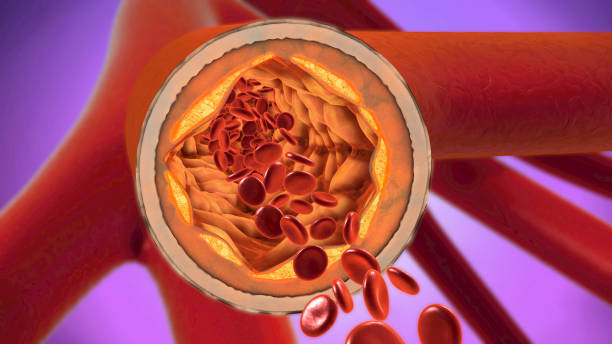

두통

뇌 혈액 공급이 감소하면 뇌 조직에 충분한 산소와 영양소가 공급되지 않아 두통이 발생할 수 있습니다. 이 두통은 대개 양쪽 머리에서 발생하며, 가벼운 것부터 매우 심한 것까지 다양한 정도가 있을 수 있습니다.